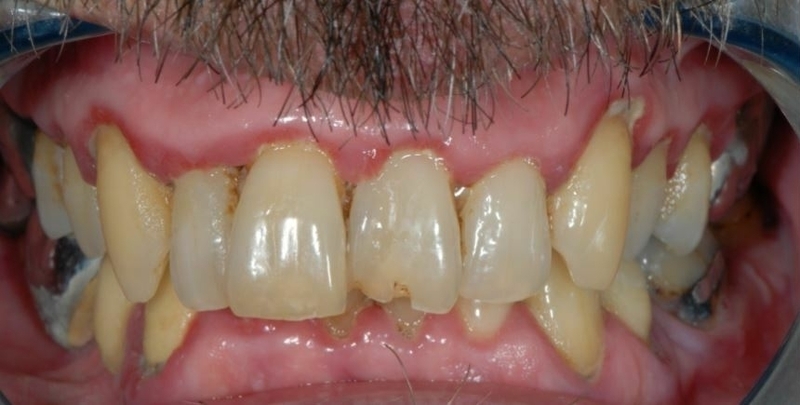

Cas 1 - Parodontie

Avant

Après